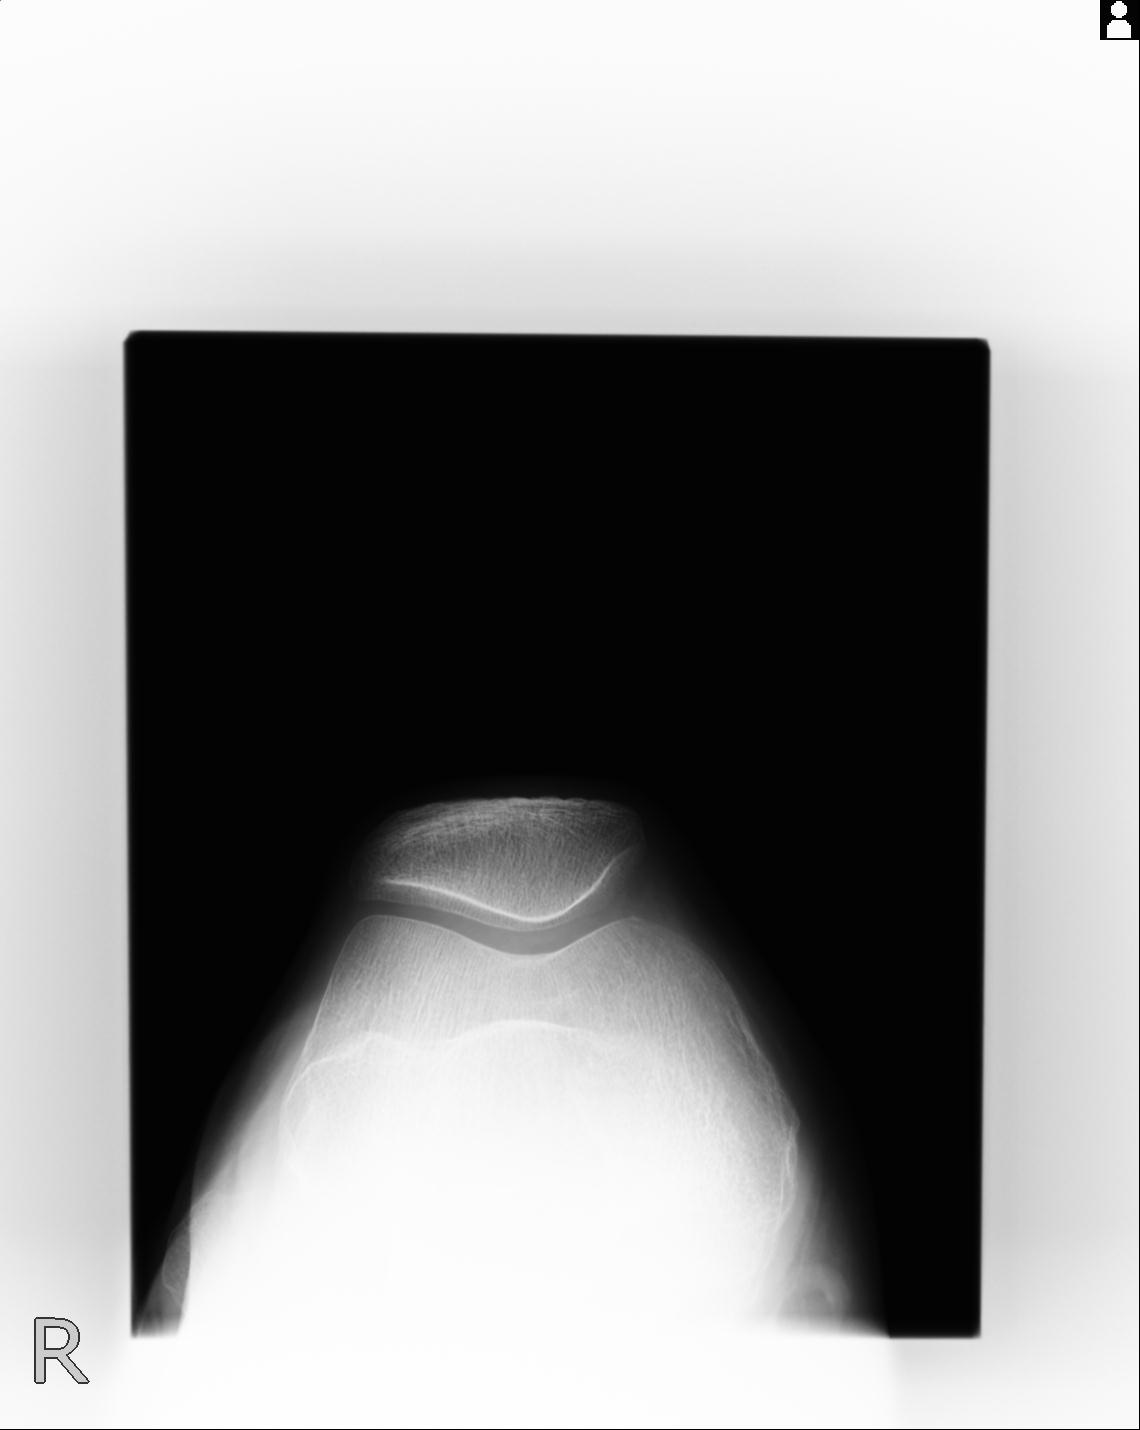

100612 11/25 1/20 右膝 2R 84歳女性 右TKA